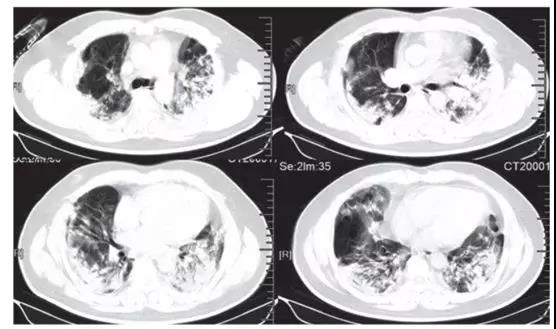

中国学者Lancet刊文称新型病毒感染有四大常见表现: 发烧、干咳、呼吸困难和双侧毛玻璃状样变!

阜外医院肺血管病房充分利用“互联网+医疗”的优势作用 开展远程线上查房